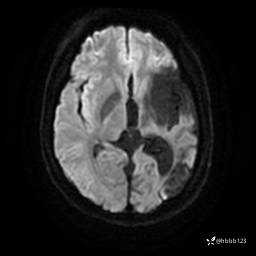

患者男,43岁。

简要病史:癫痫患者复诊,昨日发作5-6次,建议住院进一步治疗。

入院完善脑癫痫组合序列:

ADC: